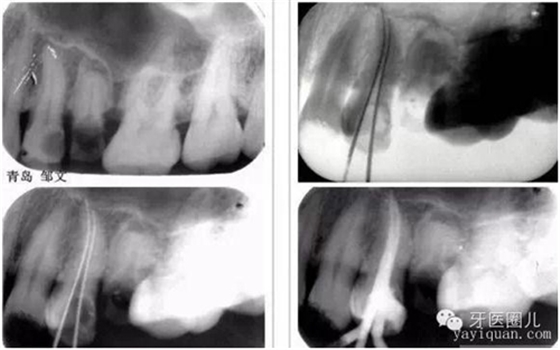

1.確定工作長(zhǎng)度(根測(cè)儀+X光片)這個(gè)大家都知道就不再贅述

觀察術(shù)前X光片,設(shè)想達(dá)到一個(gè)理想的結(jié)果,然后用這一設(shè)想來(lái)指導(dǎo)每一治療步驟,這樣自然會(huì)提高我們的根管治療的操作水平。

關(guān)于操作長(zhǎng)度應(yīng)該短于X光片的終點(diǎn),也就是我們常說(shuō)的“寧欠誤超”盡管意圖是好的,我們同行間經(jīng)??诳谙鄠?,但是短的限度是任意的,是錯(cuò)誤的信息和錯(cuò)誤的概念。牙根表面根尖孔的解剖位置和X光片上觀察到的根尖位置不相符,X光片不可能準(zhǔn)確的定位。相比X光根管測(cè)量?jī)x就準(zhǔn)確的多,盡管有時(shí)不完美,但能準(zhǔn)確定位根尖孔的位置。

過(guò)短的根尖終點(diǎn)助長(zhǎng)了碎屑的堆積和滯留也容易出現(xiàn)臺(tái)階和穿孔。操作長(zhǎng)度短經(jīng)常導(dǎo)致根管治療的失敗;所以說(shuō)根測(cè)儀在治療中是必須的,省不了的。